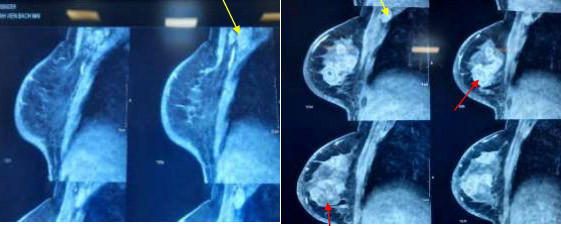

22/12/2022 17:23Trì hoãn đi khám, người phụ nữ nhận kết quả mắc ung thư di căn

Bệnh nhân là chị T.T.H. nữ (46 tuổi) đang điều trị ung thư vú thể viêm tại Trung tâm Y học hạt nhân và Ung bướu, Bệnh viện Bạch Mai.

Trước đó, tháng 3/2021, người phụ nữ này tự sờ thấy khối u vú bên phải, không đau, không sưng. Khối u tiến triển kích thước to dần. Tháng 7/2021, khối u của chị xuất hiện sưng, đỏ, không chảy dịch mủ, đau nhiều đặc biệt khi sờ nắn. Tuy nhiên, chị H. không sốt, không sút cân.

Người phụ nữ này đi khám được điều trị kháng sinh, giảm đau nhiều đợt nhưng khối u không đáp ứng, tiếp tục tăng kích thước.

Do dịch Covid 19, bệnh nhân trì hoãn không đi khám và điều trị. Tháng 12/2021, chị H. khám tại Bệnh viện Bạch Mai trong tình trạng còn đau vú, không sốt, không sút cân. Sau đó, bệnh nhân được sinh thiết tổn thương với kết quả là mắc ung thư biểu mô tuyến vú xâm nhập. Với chẩn đoán ung thư vú phải thể viêm (giai đoạn IIIB), bệnh nhân được điều trị hóa chất, chu kỳ 3 tuần (điều trị 6 chu kỳ).

PGS.TS Phạm Cẩm Phương, Giám đốc Trung tâm Y học hạt nhân và Ung bướu, Bệnh viện Bạch Mai, cho biết bệnh nhân trong ca lâm sàng này đã phát hiện u vú từ thời điểm tháng 3/2021. Khối u vú phát triển nhanh sau 4 tháng với biểu hiện điển hình của ung thư vú thể viêm, điều trị kháng sinh không đỡ.

Do bệnh nhân không được tiếp cận và điều trị ở ngay thời điểm này. Bệnh nhân đến viện khi đã xuất hiện ung thư vú thể viêm đa ổ, di căn hạch nách, chưa di căn xa.

“Người bệnh được hội chẩn tiểu ban vú, tiến hành điều trị đa mô thức, trước tiên là điều trị hoá chất tân bổ trợ. Sau một chu kỳ hóa chất, bệnh nhân ổn định”, PGS.TS Phương thông tin.

Theo các bác sĩ, đây là một dạng ung thư vú tiến triển nhanh, hiếm gặp với tỷ lệ 0,5-2% trong tổng số các trường hợp ung thư vú xâm lấn tại Mỹ.

Bệnh nhân ung thư vú thể viêm thường đến khám với khối u vú tiến triển nhanh hoặc vú sưng đau không cải thiện sau điều trị kháng sinh. Biểu hiện lâm sàng thường gặp là vú sưng đỏ tối thiểu 1/3, nóng, da phù, sần da cam, có hoặc không sờ thấy khối, thường tiến triển nhanh không quá 6 tháng kể từ khi khởi phát triệu chứng.

Chẩn đoán ung thư vú thể viêm dựa vào các đặc điểm lâm sàng và giải phẫu bệnh trên bệnh phẩm sinh thiết. Ung thư vú thể viêm có tiên lượng xấu, nguy cơ tái phát cao.

Nguyên tắc điều trị ung thư vú thể viêm chưa di căn xa tương tự ung thư vú giai đoạn tiến triển khác. Điều trị đa mô thức bao gồm phối hợp hóa chất tân bổ trợ, phẫu thuật và xạ trị hậu phẫu.